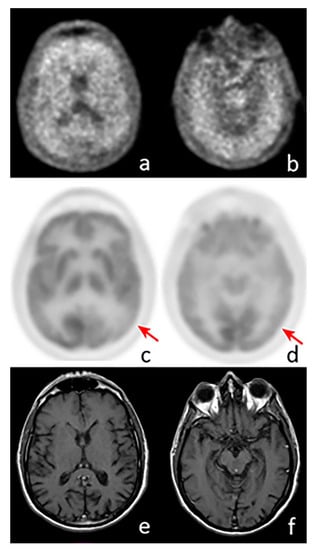

2.1. FDG Imaging in AD

3.1. FDG-PET in FTD

4.3. FDG-PET Imaging in SNCApathies

5.1. FDG-PET Imaging in Atypical Parkinsonian Syndromes